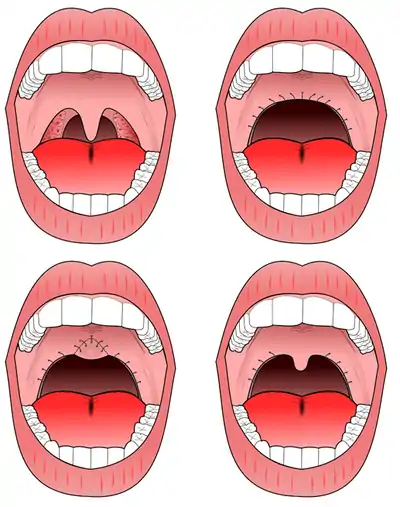

Uvulopalatopharyngoplasty (UPPP)

The procedure most commonly performed for sleep apnea is the uvulopalatopharyngoplasty (UPPP). This involves removal of the tonsils if still present, and a subsequent palatal procedure. The tonsil pillars are often sutured closed—and the uvula is either trimmed, cut, folded, reshaped, or sutured to the soft palate.[7] Studies have shown that treatment effect of UPPP with tonsillectomy increases with tonsil size.[8]